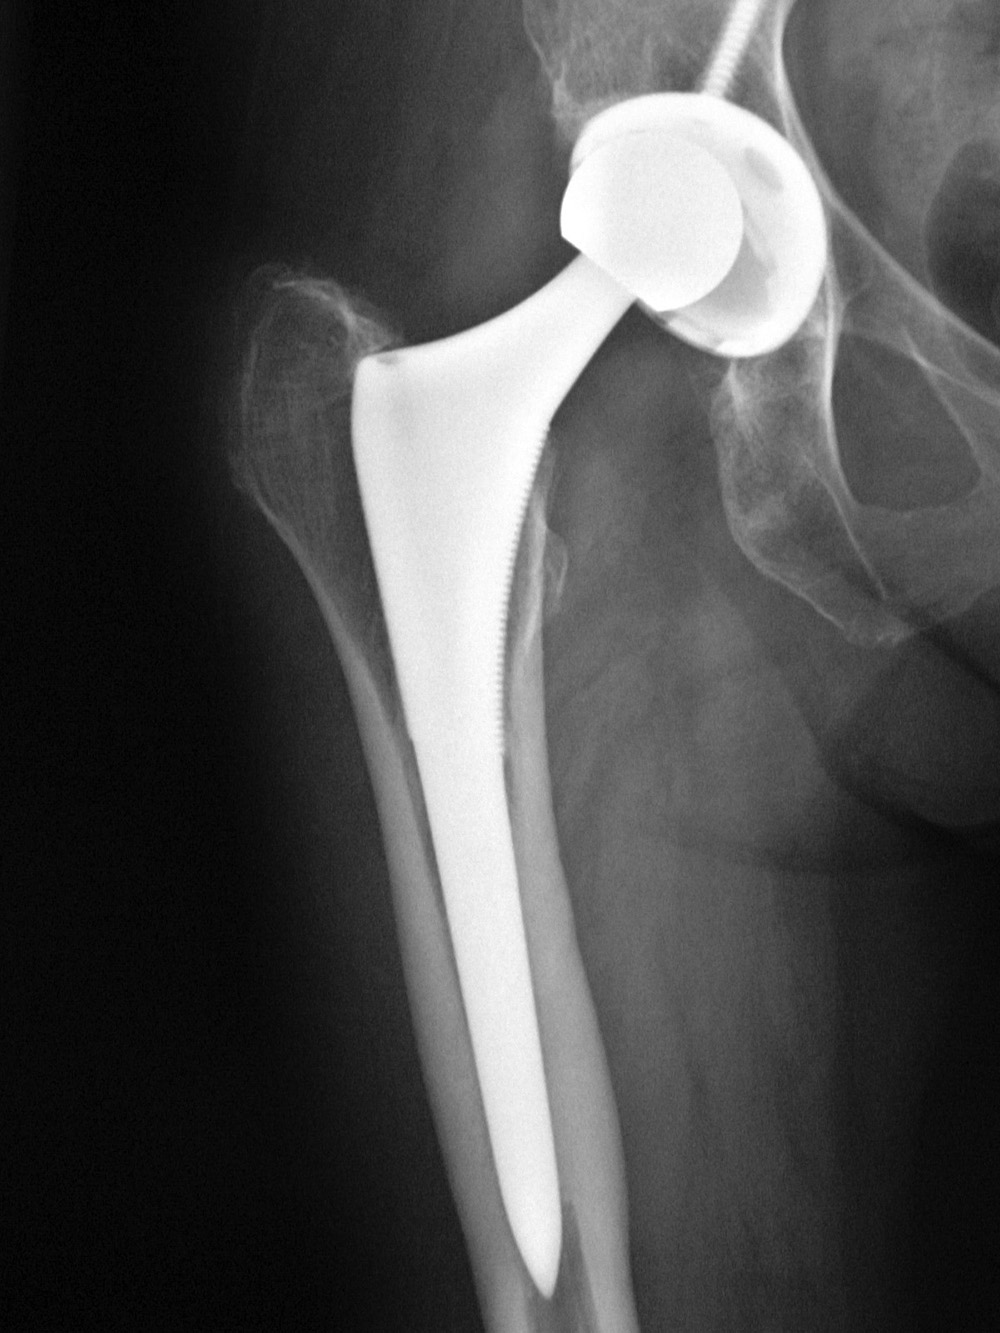

Хирургическая замена тазобедренного сустава, также известная, как эндопротезирование, включает в себя хирургическое удаление пораженной части бедра и замены его новым протезом. Каждый год в Соединенных Штатах выполняется более 332,000 операций по замене тазобедренного сустава .

Они объясняют, что тазобедренные протезы служат менее 20 лет, так что, вполне вероятно, что более молодым пациентам в один прекрасный день потребуется вторая операция по замене тазобедренного сустава. Замена изношенного протеза тазобедренного сустава является технически сложной операцией, и это может увеличить риск инфекции у пациентов и привести к повреждению окружающей кости.

Замена тазобедренного сустава

Искусственный тазобедренный сустав

Артроз тазобедренного сустава, который сегодня часто лечится полным эндопротезированием (ТЭП), является одним из наиболее частых дегенеративных заболеваний суставов. Ежегодно в Германии устанавливается около 200 000 протезов тазобедренного сустава.

Преимущества протезирования тазобедренного сустава

Перед операцией процедура должна обсуждаться с пациентом и планироваться на основе рентгеновского обследования. Во время операции изношенные суставные части удаляются и заменяются искусственными. Как правило, это приводит к облегчению боли и улучшению функции тазобедренного сустава. Однако, поскольку со временем может произойти ослабление протеза, для пожилых пациентов, как правило, рекомендуется полная замена сустава.

Протез тазобедренного сустава может быть с цементной, бесцементной или смешанной фиксацией (например, цементированная гильза и безцементная вертлужная впадина).

Кроме того, могут потребоваться корректировки костной ткани или структуры. В данной области суставы представляют собой различные комбинации материалов, например: керамики, металла или полиэтилена.

Риски при тазобедренном эндопротезировании

Сразу после операции может возникать кровотечение, сосудистые окклюзии, эмболия легких или повреждения нервов/сосудов. Со временем искусственный сустав может расшататься, что потребует замены тазобедренного протеза. Это способно привести к дислокациям (вывихам) протеза или недостаточному уменьшению боли, с которой ранее могли справляться.

Что следует учитывать после имплантации эндопротеза тазобедренного сустава?

Сразу же после установки искусственного сустава необходимо провести рентгенологическое обследование, чтобы проверить положение протеза. Пациенты должны начать двигаться как можно раньше, чтобы избежать атрофии мышц. С помощью физиотерапии и последующего лечения («реабилитация») стараются восстановить прежнюю мобильность пациента.:max_bytes(150000):strip_icc()/hip-replacement--illustration-1155266197-3a4fe05bca314a5fbeeb7336a0d55067.jpg)

Чтобы не допустить косвенных повреждений, пациенты с протезом тазобедренного сустава должны избегать чрезмерной физической нагрузки, нормализовать свой вес и регулярно проходить проверки у соответствующих специалистов.